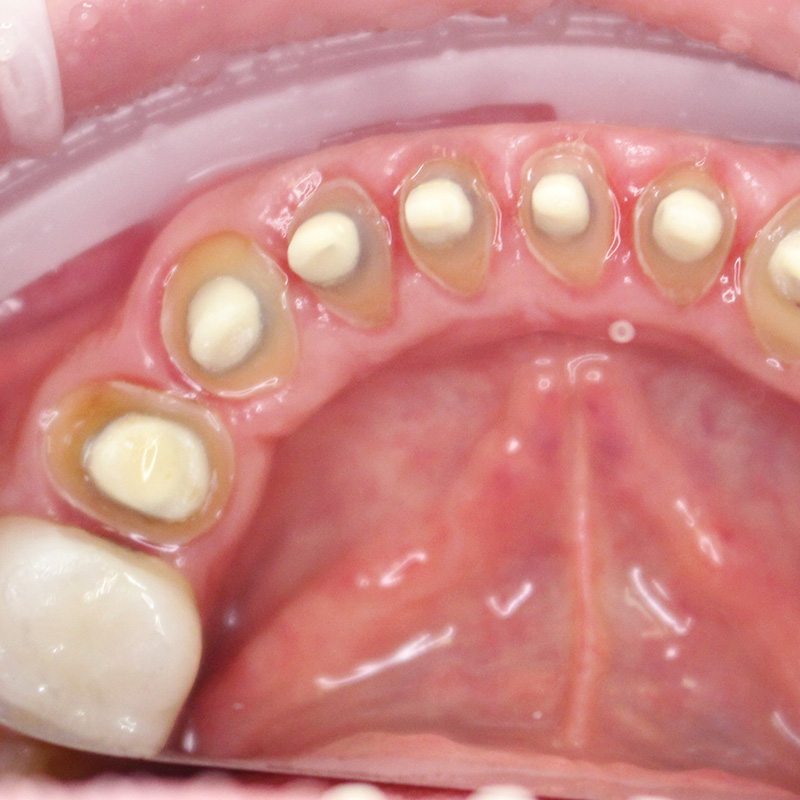

В нашу клинику обратился пациент с жалобами частично-разрушенные зубы нижней челюсти.

На момент осмотра была выявлена необходимость в протезировании 9-ти нижних зубов.

В ходе процедуры были проведены следующие работы:

- профессиональная гигиена полости рта;

- пролечивание зубов и укрепление их культевыми вкладками с керамической облицовкой;

- снятие слепков с обеих челюстей;

- установка диоксид-циркониевых коронок на зубы 35-44.